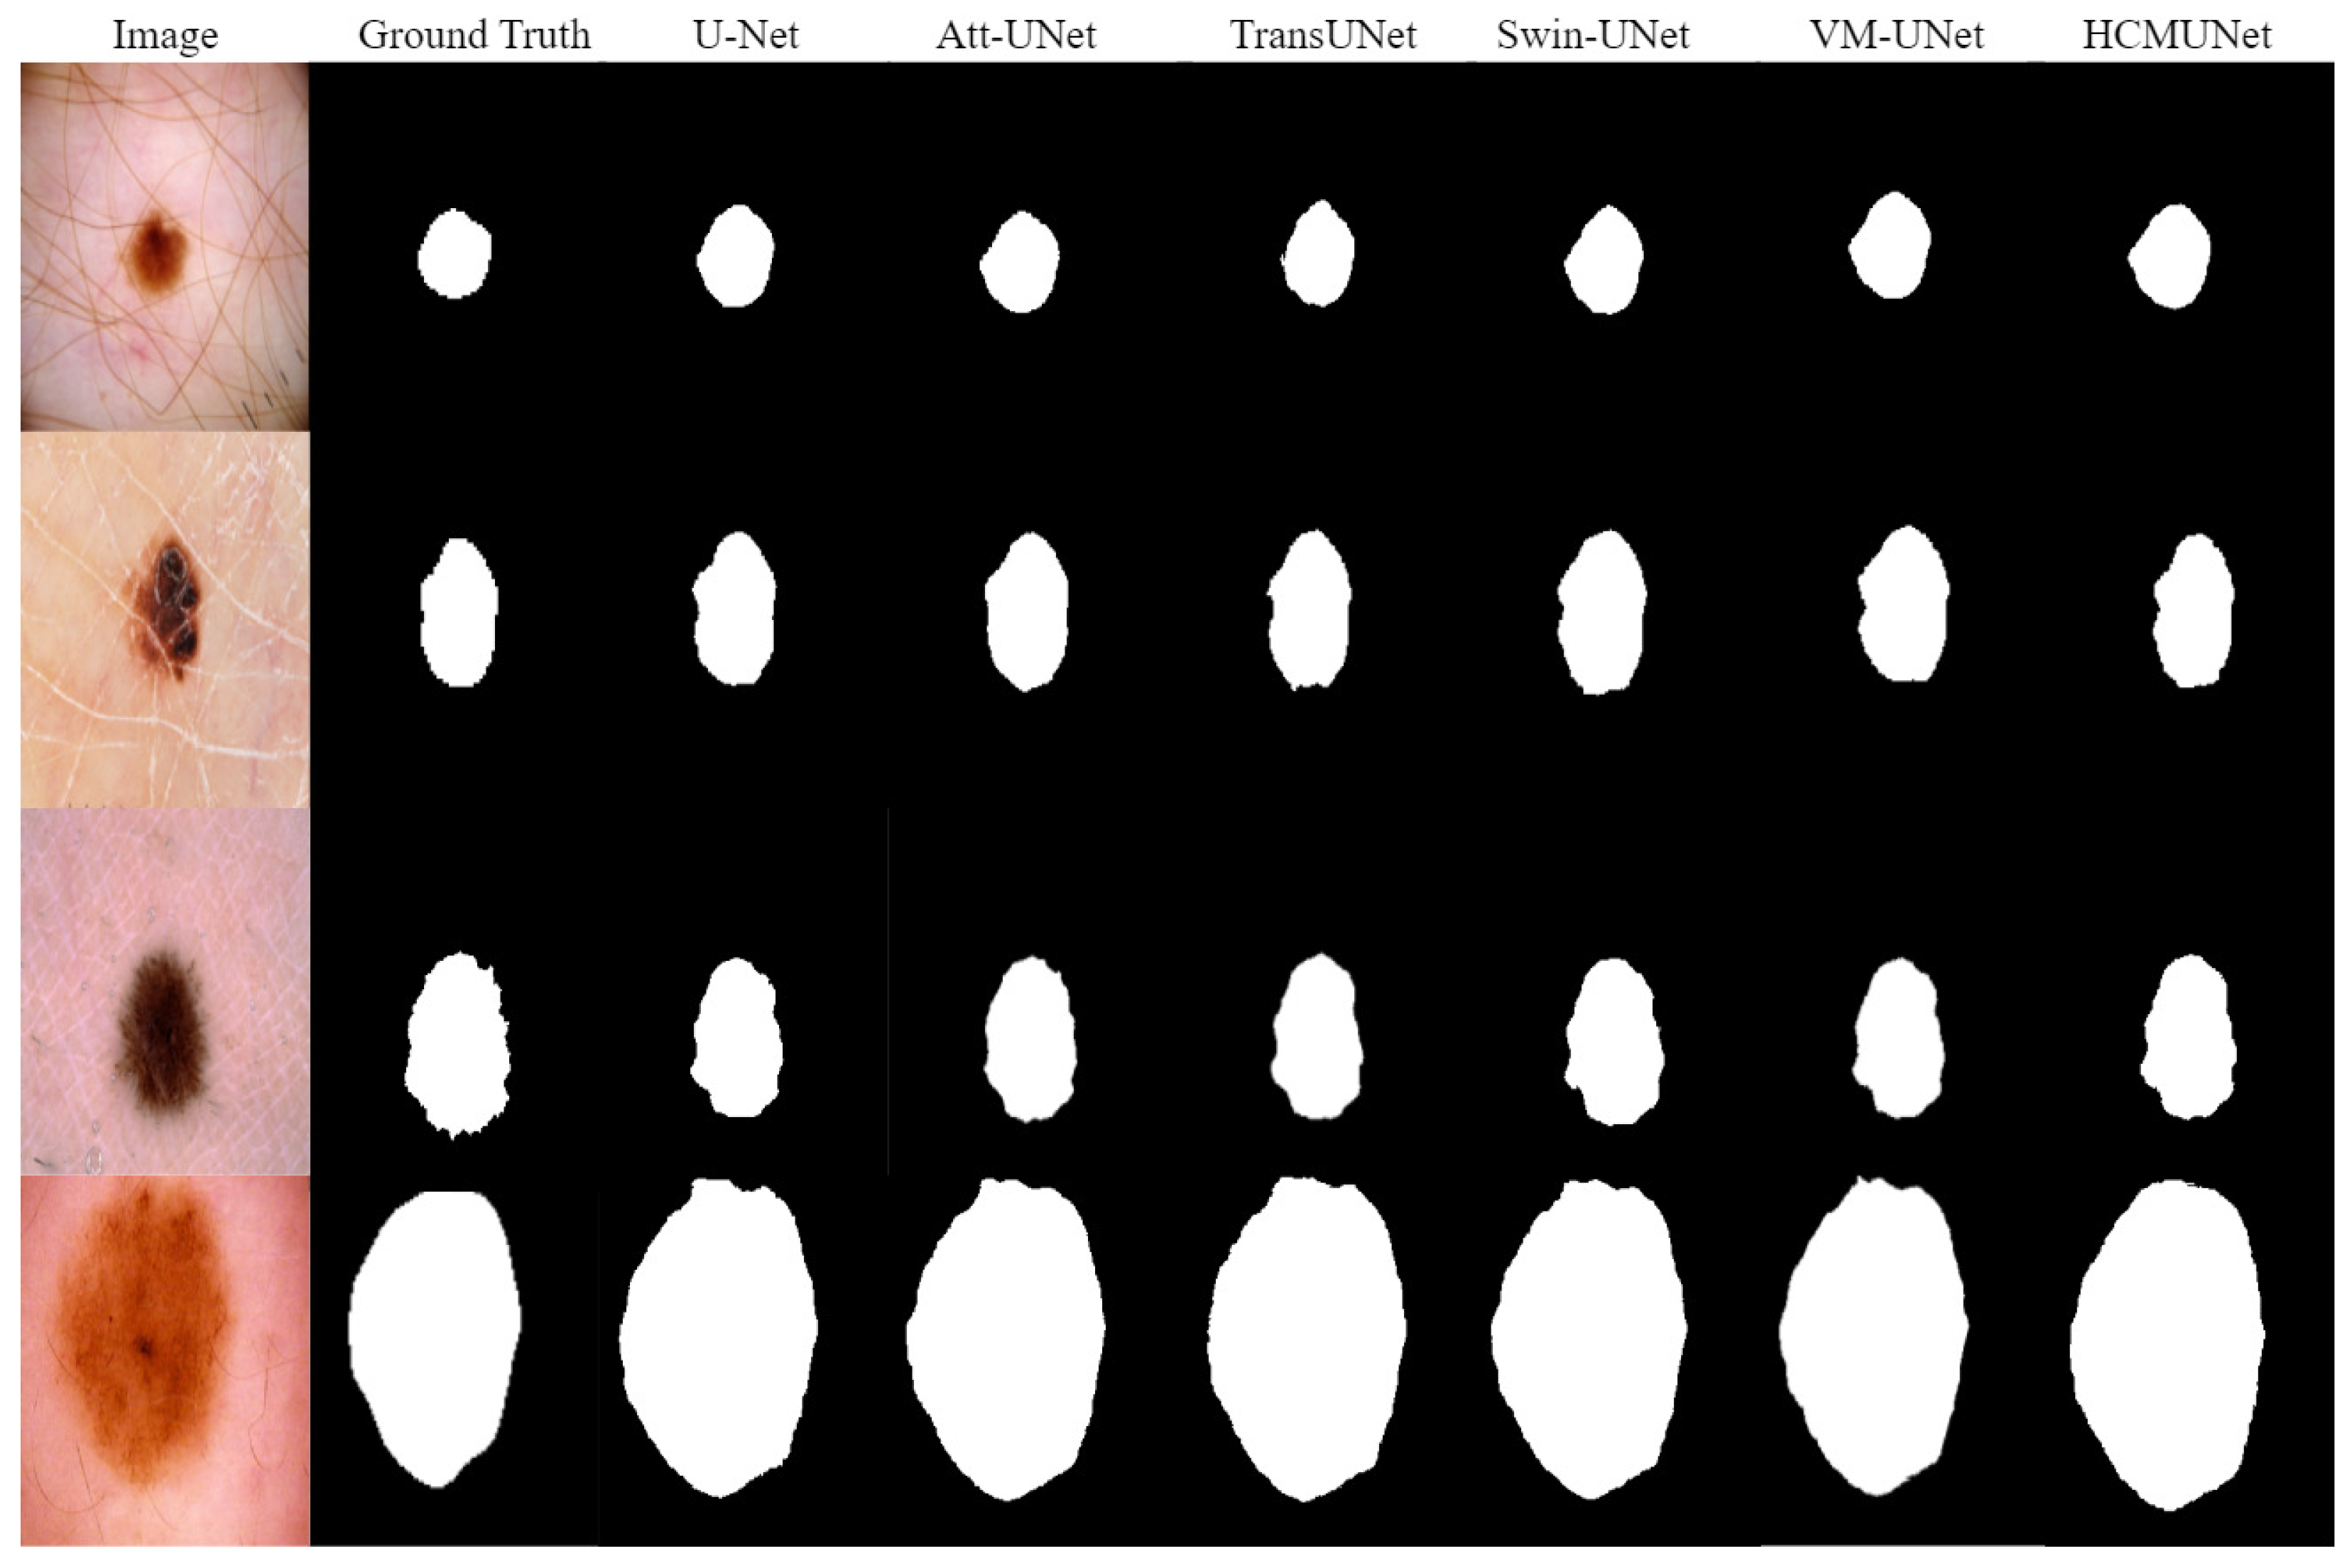

| Model | mIoU (%) | DSC (%) | Acc (%) | Spe (%) | Sen (%) |

|---|---|---|---|---|---|

| U-Net [2] | 77.64 ± 0.73 | 87.42 ± 0.87 | 93.88 ± 0.95 | 96.32 ± 1.20 | 87.71 ± 1.44 |

| U-Net++ [17] | 78.30 ± 0.90 | 87.63 ± 0.71 | 93.76 ± 0.78 | 95.19 ± 1.07 | 88.10 ± 1.23 |

| Att-UNet [19] | 78.95 ± 1.17 | 87.91 ± 1.01 | 93.21 ± 1.15 | 96.23 ± 1.35 | 87.60 ± 1.53 |

| SANet [42] | 79.47 ± 1.29 | 88.42 ± 1.11 | 94.29 ± 0.69 | 95.57 ± 1.42 | 89.46 ± 1.37 |

| TransUNet [43] | 79.71 ± 1.20 | 88.52 ± 1.27 | 94.57 ± 1.41 | 96.05 ± 1.30 | 89.14 ± 1.19 |

| TransFuse [44] | 80.66 ± 1.25 | 89.33 ± 1.28 | 93.66 ± 0.67 | 93.73 ± 1.17 | 90.78 ± 1.45 |

| Swin-UNet [26] | 80.71 ± 1.13 | 89.66 ± 1.04 | 94.19 ± 0.78 | 95.41 ± 1.22 | 90.31 ± 1.10 |

| VM-UNet [12] | 81.27 ± 0.79 | 89.67 ± 0.68 | 94.83 ± 0.63 | 96.13 ± 1.01 | 90.79 ± 0.98 |

| HCMUNet (Ours) | 82.19 ± 0.62 | 90.32 ± 0.53 | 94.71 ± 0.70 | 96.19 ± 0.78 | 91.21 ± 0.80 |